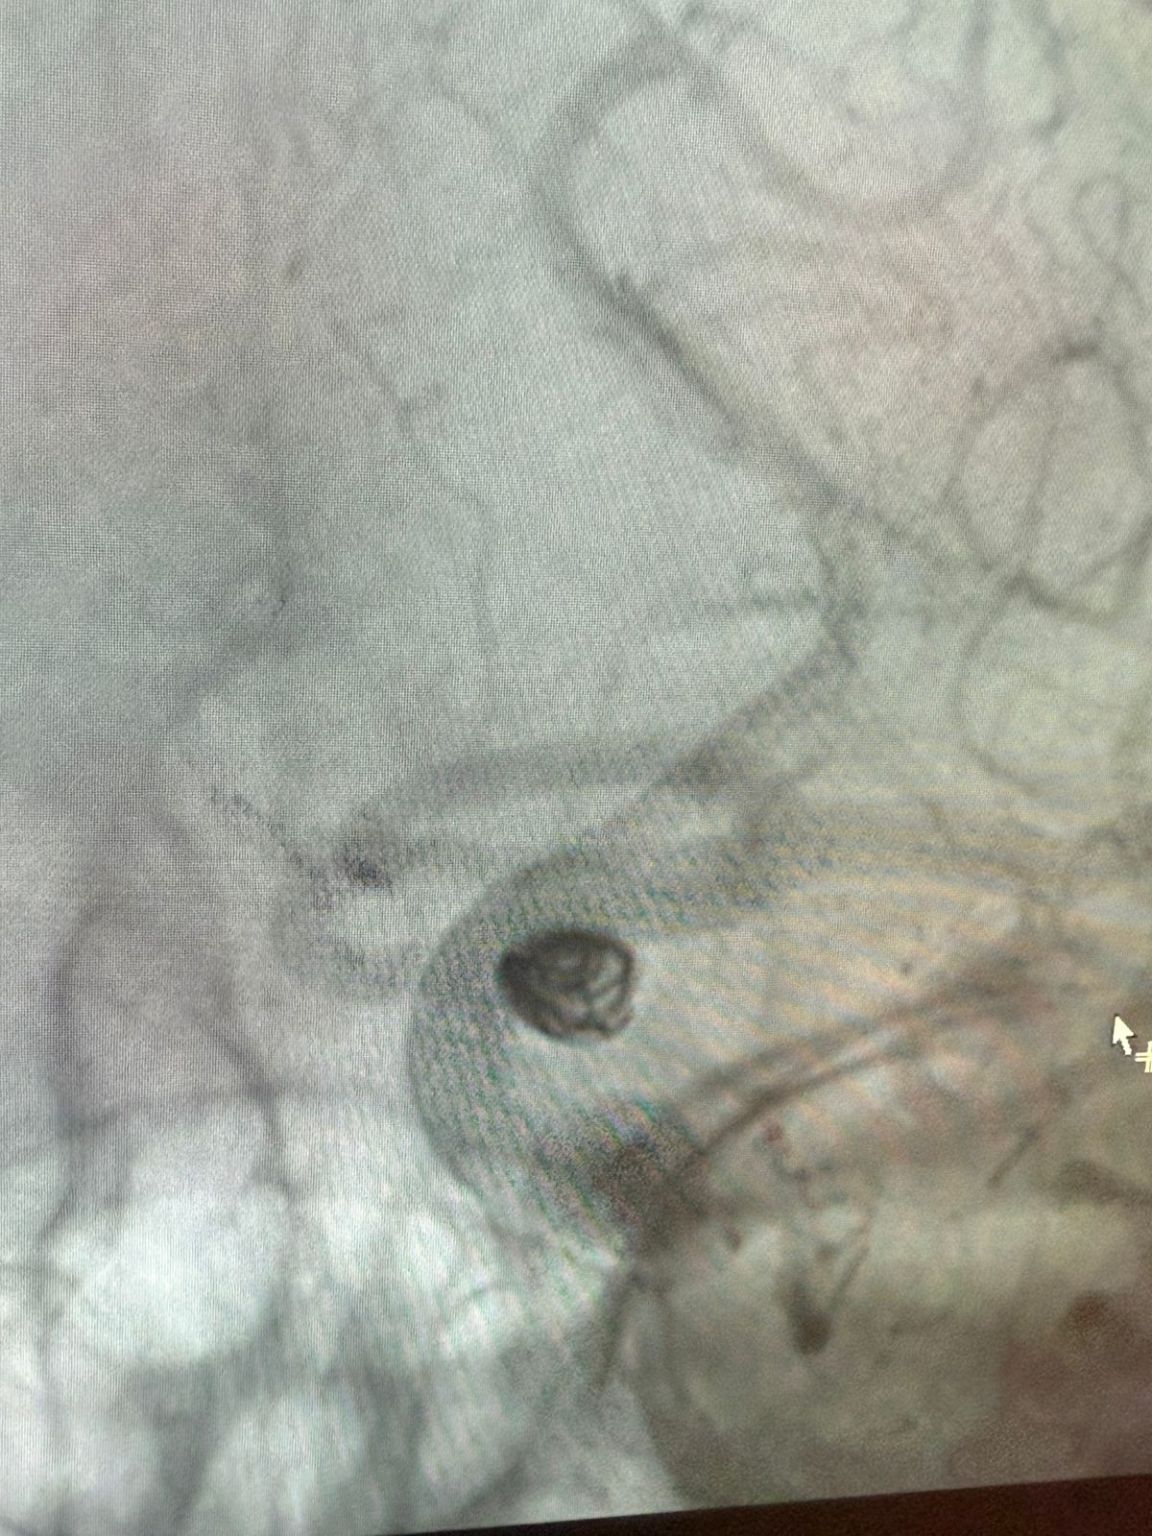

治療はNuvaを利用しました®流れのダイバーター (5.0-14 TJED-D) 、Perdenser®3Dコイル、およびFrepass®後部通信動脈動脈瘤用のマイクロカテーテル (TJMC18 Plus)。

Mutis博士は、デバイスの優れた視認性を強調し、回収がスムーズであると述べました。 彼は最終結果に大きな満足を表明した。